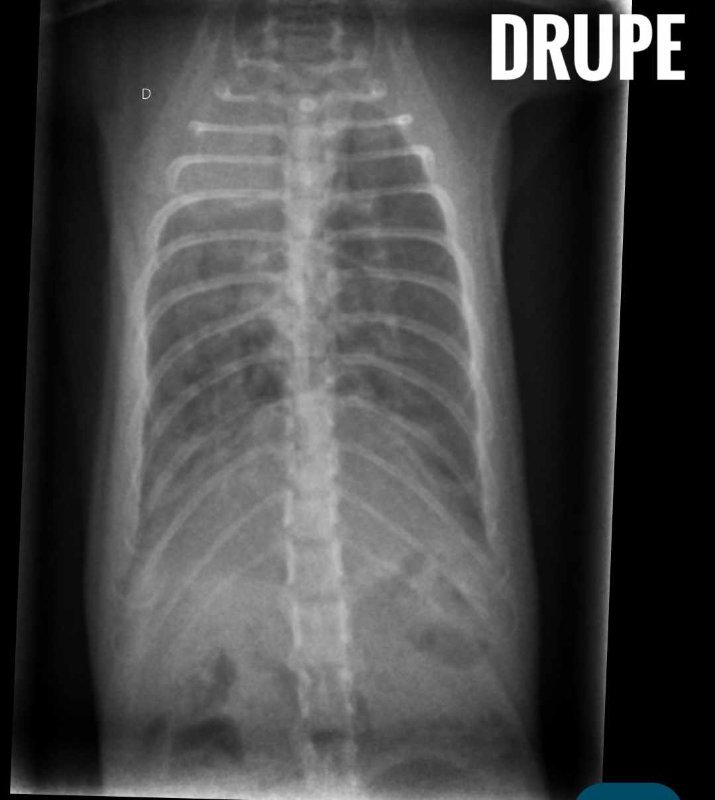

-Drupe, l'actuel plus touché, je vous joins la radio, elle est tellement inquiétante que ça me tue ;

J'ai mis les radios de Drupe du 26/01, et les deux radios de Caryopse, pour ceux qui seraient curieux. Idem, j'ajoute les courbes de poids, j'ai un suivi au jour le jour, des fois que ça intéresse des gens (si vous voulez que j'enlève les noms de médocs dessus pour plutôt mettre les noms de molécules, je peux, pas de soucis).